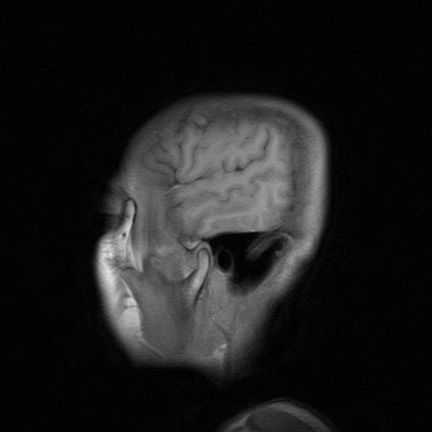

标题: MRI2064:少见病例。男性52,视力下降多年。 [打印本页]

标题: MRI2064:少见病例。男性52,视力下降多年。

四脑室区见混杂信号占位影,脑室系统扩张明显,临近结构显著受压称位,患者52岁,多考虑室管膜瘤可能性大

考虑第四脑室室管膜瘤并阻塞性脑积水。

考虑第四脑室室管膜瘤并梗阻性脑积水;部分性空蝶鞍;左侧上颌窦粘膜下囊肿。

考虑第四脑室室管膜瘤【血供丰富血管母细胞瘤可能】并梗阻性脑积水;部分性空蝶鞍;左侧上颌窦粘膜下囊肿。

比较典型的脉络丛乳头状瘤并脑积水,鉴别小脑蚓部血管母细胞瘤。